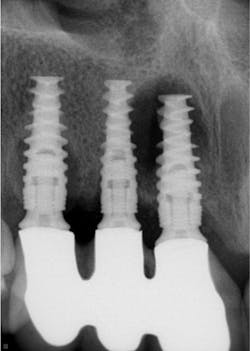

Historically, with a few exceptions, crowns did not come off in service. Zinc phosphate and conventional GI cements are rigid and strong and held the crowns on the tooth preparations. Resin cements are flexible and strong (figure 3). But one of the major reasons almost every dentist has had zirconia crowns coming off is the flexibility of resin cements and, to a lesser degree, the flexibility of the RMGI cements (figure 4).

Dentists need rigid, strong, cariostatic cements almost every day of practice. As with composite restorative materials, resin cements need cariostatic properties immediately! In the interim, until resin cements are modified, I suggest that dentists should use RMGI and GI cements for crowns and fixed prostheses.